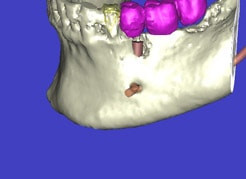

In komplexen Fällen, z. B. der Implantatversorgung eines kompletten Kiefers, oder bei schwierigen Knochensituationen bietet die 3-dimensionale Computerdiagnostik bzw. Planung und Durchführung erhebliche Vorteile und Sicherheit für den Patienten (siehe Bild 1 und 2).

Computerdarstellung des Kiefers mit geplanter Implantatposition

Auf Basis einer computertomografischen (CT-) Kieferaufnahme ist eine dreidimensionale Darstellung der Knochen möglich. Der Zahnarzt kann dann am Computerbildschirm die Knochenqualität (z. B. Knochendichte) beurteilen und die optimale Position der Implantate im Vorfeld planen. Durch Verwendung spezieller Röntgenschablonen lässt sich auch die erwünschte Zahnstellung in die Planung einbeziehen. Die Simulation der OP erlaubt, das zu erwartende Ergebnis mit größtmöglicher Sicherheit vorherzusagen und dem Patienten am Bildschirm zu veranschaulichen.

(siehe Bild 3 und 4).

Mit diesen gewonnenen Informationen und Planungen stellt der Zahnarzt interaktiv spezielle Bohrschablonen her. Diese ermöglichen eine exakte Positionierung der Implantate, so wie vorher am Computer geplant.

Weiterhin ist eine auf diese Weise geplante Operation für den Patienten weit weniger belastend. Denn die Freilegung des Knochens ist auf ein Minimum reduziert.